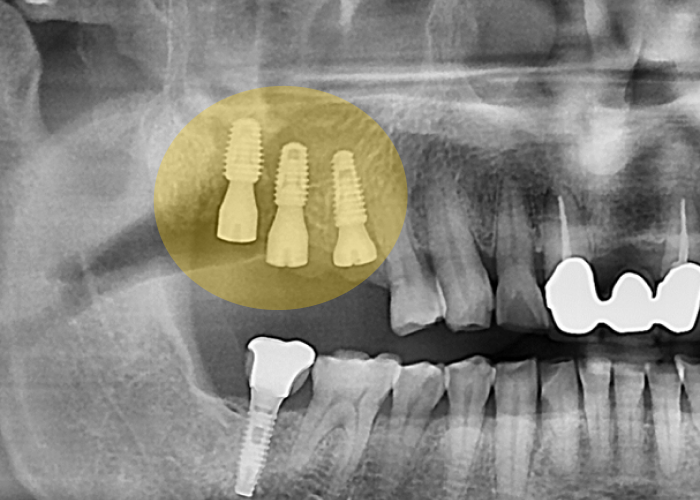

발치 직후

어려운 조건이었지만,

울산 어금니임플란트를 단단하게 심어

안정적인 고정을 확보했습니다.

맞춤형 어버트먼트를

체결한 모습입니다.

맞춤형 어버트먼트는

디지털 스캔 데이터를 기반으로

잇몸 곡선을 그대로 반영해 제작되므로,

보철물이 올라갔을 때

잇몸과 자연스럽게 이어지고

위생 관리도 수월합니다.